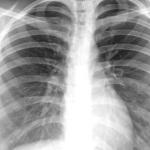

Китай стартира клинични изпитвания на иновативна иРНК ваксина срещу туберкулоза, разработена самостоятелно. Тестовете се провеждат в Пекинската болница за гръдни заболявания, съобщава Синхуа.

Паралелно с ваксината, болницата въведе интелигентен диагностичен модел, базиран на изкуствен интелект (AI). Той използва тампони от езика за бързо откриване на туберкулозния бацил.

Този иновативен метод позволява неинвазивно и дистанционно ранно диагностициране на белодробни заболявания, включително туберкулоза. В момента е в предклиничен етап, като се очаква масово внедряване в цялата страна от юли.